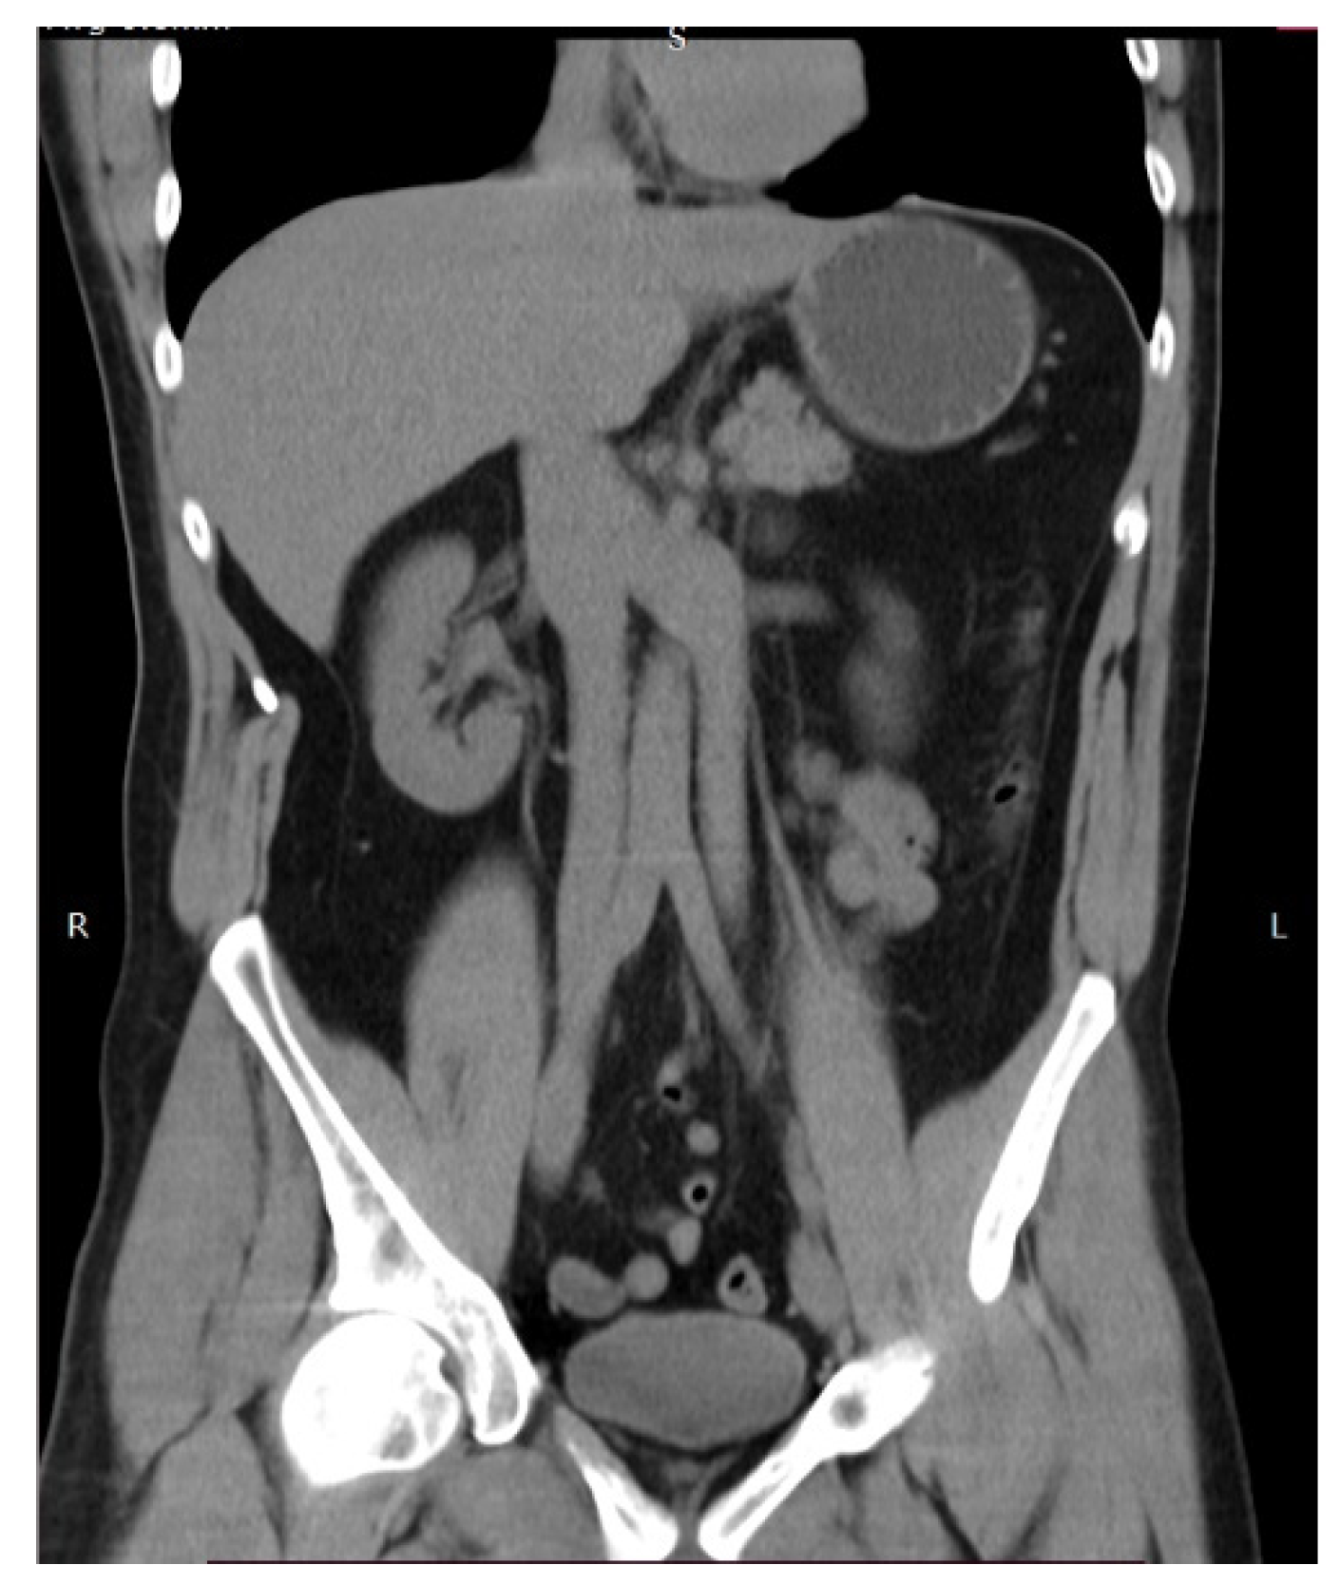

- The aortocaval or interaortocaval region (includes preaortic and precaval PALNs) is limited: ventrally—LRV, laterally—left—lateral aspect of the AA, right—lateral aspect of inferior vena cave, dorsally—AA bifurcation, caudally—prevertebral fascia, anterior longitudinal ligament and psoas major muscle.

- The paracaval region (includes laterocaval and retrocaval PALNs) is limited: ventrally—right renal vein (RRV); dorsally—midpoint of the lateral aspect of right CIA, laterally—right ureter and right psoas major muscle, caudally—the psoas major muscle.